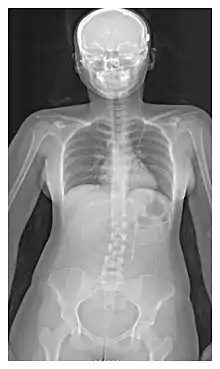

The location of the shunt is determined by the neurosurgeon based on the type and location of the blockage causing hydrocephalus. All brain ventricles are candidates for shunting. The catheter is most commonly placed in the abdomen but other locations include the heart and lungs.[10] Shunts can often be named after the route used by the neurosurgeon. The distal end of the catheter can be located in just about any tissue with enough epithelial cells to absorb the incoming CSF. Below are some common routing plans for cerebral shunts.

| Ventriculo-peritoneal shunt (VP shunt) | Peritoneal cavity |

| Ventriculo-atrial shunt (VA shunt) | Right atrium of the heart |

| Ventriculo-pleural shunt (VPL shunt) | Pleural cavity |

| Ventriculo-cisternal shunt (VC shunt) | Cisterna magna |

| Ventriculo-subgaleal shunt (SG shunt) | Subgaleal space |

| Lumbar-peritoneal shunt (LP shunt) | Peritoneal cavity |